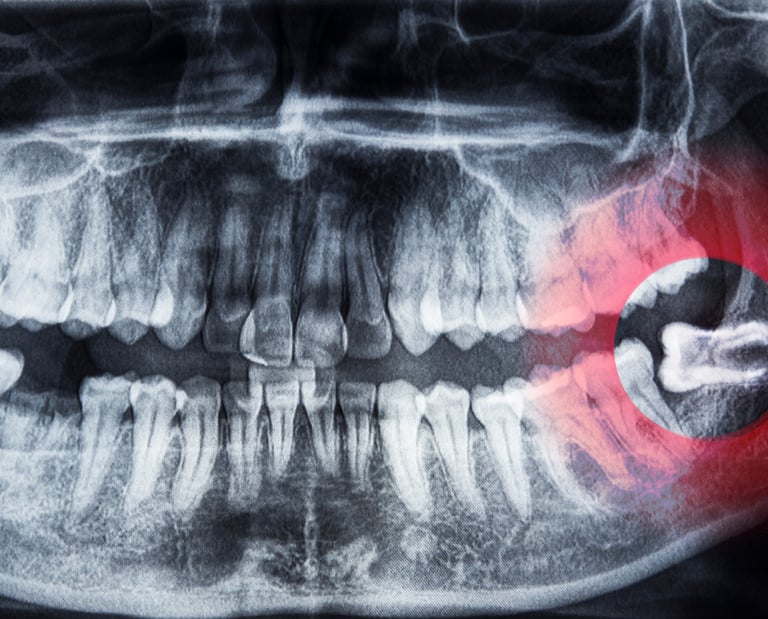

1. Wisdom Tooth Removal

The third molars, commonly known as wisdom teeth, often don’t have enough room to erupt properly. This can lead to crowding, infections, or pain. Our oral surgeons safely remove impacted or partially erupted wisdom teeth, preventing complications and ensuring a smooth recovery.